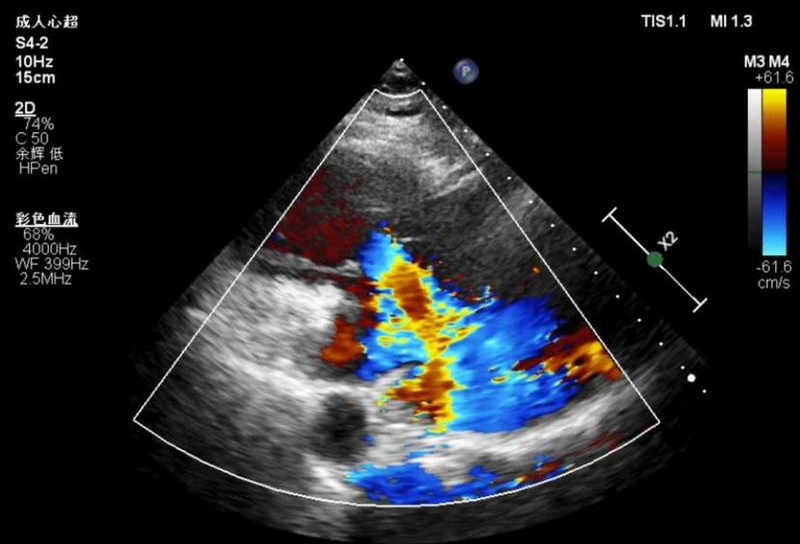

一根经颈内静脉输送的特制导管,将精巧的K‑Clip®夹合装置准确送入患者心脏。在超声实时引导下,手术团队通过微小的血管通路,对患者扩大的三尖瓣环进行精准修复。这是仁济医院宝山分院成功开展的K‑Clip®经导管三尖瓣环成形术,为一位极重度三尖瓣反流患者实施微创治疗的真实场景。

术后评估显示,患者三尖瓣反流程度从术前的极重度降至中度,临床症状得到显著改善。李女士目前也已在康复中。